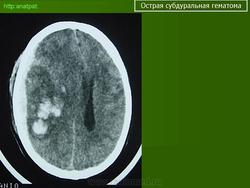

Субдуральные гематомы представляют собой кровоизлияние между твердой мозговой оболочкой и паутинной оболочкой, непосредственно покрывающей мозг, и обычно происходят вследствие разрыва сосуда на поверхности мозга. В большинстве случаев Субдуральные гематомы располагаются на обширной территории над лобными и теменными долями. Острые субдуральные гематомы - это кровоизлияния, произошедшие в сроки до 72 часов и выглядящие на КТ головного мозга как гиперденсивные образования. Подострые субдуральные гематомы это кровоизлияния от 3 до 20 дней, которые на КТ выглядят как изоденсные или гиподенсные относительно головного мозга образования. Хронические Субдуральные гематомы - это гематомы старше 21 дня (3 недель), которые выглядят, как гиподенсные образования на КТ. Тем не менее, Субдуральные гематомы могут быть смешанными, например, когда происходит острое кровоизлияние в полость хронической гематомы. Острые субдуральные гематомы встречаются у 5-25% пациентов с тяжелой черепно-мозговой травмой. Хронические субдуральные гематомы насчитывают 1-5.3 на 100 000 населения в год. Более свежие исследования демонстрируют более высокую частоту гематом в связи с улучшением техники нейровизуализации. В противоположность эпидуральным гематомам, которые обычно не распространяются за пределы костных швов черепа, субдуральные гематомы могут быть очень протяженными по площади, распространяясь от серпа мозга до намета мозжечка. Острые субдуральные гематомы вследствие травмы наиболее опасные из всех повреждений мозга, сопровождающиеся наибольшей летальностью, если вовремя не провести хирургическое вмешательство.

Острая субдуральная гематома.

Острые субдуральные гематомы - это кровоизлияния, произошедшие в сроки до 72 часов и выглядящие на КТ головного мозга как гиперденсивные образования. Подострые субдуральные гематомы это кровоизлияния от 3 до 20 дней, которые на КТ выглядят как изоденсные или гиподенсные относительно головного мозга образования. Хронические Субдуральные гематомы - это гематомы старше 21 дня (3 недель), которые выглядят, как гиподенсные образования на КТ. Тем не менее, Субдуральные гематомы могут быть смешанными, например, когда происходит острое кровоизлияние в полость хронической гематомы. Острые субдуральные гематомы встречаются у 5-25% пациентов с тяжелой черепно-мозговой травмой. Хронические субдуральные гематомы насчитывают 1-5.3 на 100 000 населения в год. Более свежие исследования демонстрируют более высокую частоту гематом в связи с улучшением техники нейровизуализации.